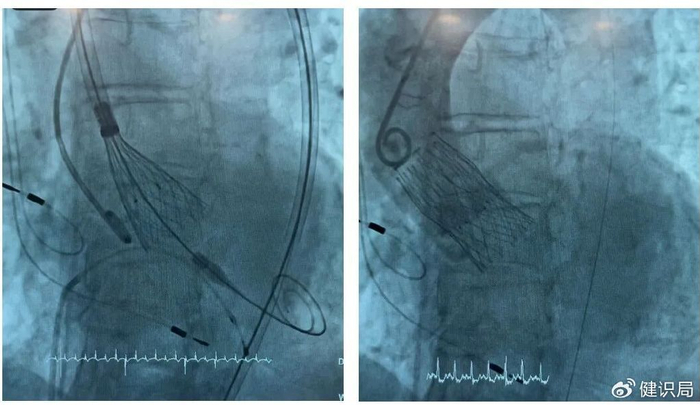

在IMPERIA输送系统获批后联合ALLEGRA心脏瓣膜于西班牙、德国完成全球首植后不久,意大利也传来喜讯,于那不勒斯Pineta Grande医院成功实现IMPERIA输送系统与ALLEGRA的联合植入。该植入针对一位高龄女性患者,由Arturo Giordano博士、Nicola Corcione博士、Michele Albanese博士和Alberto Morello博士团队完成,蓝帆柏盛国际团队现场支持。

该患者是一名83岁的女性,植入后获得卓越的临床结果:术前平均跨瓣压差:40 mmHg;术后平均跨瓣压差:8 mmHg;术后无瓣周漏发生。

放置中和放置后